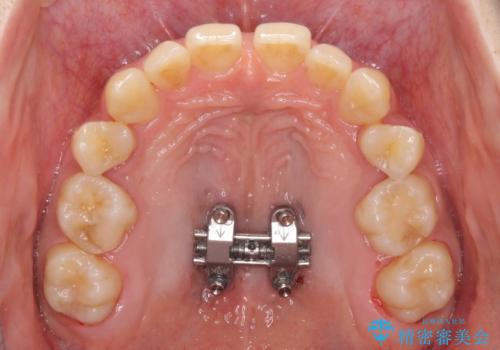

- 矯正装置

- インビザライン

反対咬合は上顎骨の幅が下顎骨よりも小さいことが原因なので、拡大装置により骨幅を広げて上下関係を改善し、その後インビザラインにて歯並びを整えることとしました。

上顎骨を拡大したことで前歯に隙間ができ、1ヶ月ほど恥ずかしい時期がありましたが、しっかりとした咬み合わせに仕上がり、患者様には大変満足していただきました。